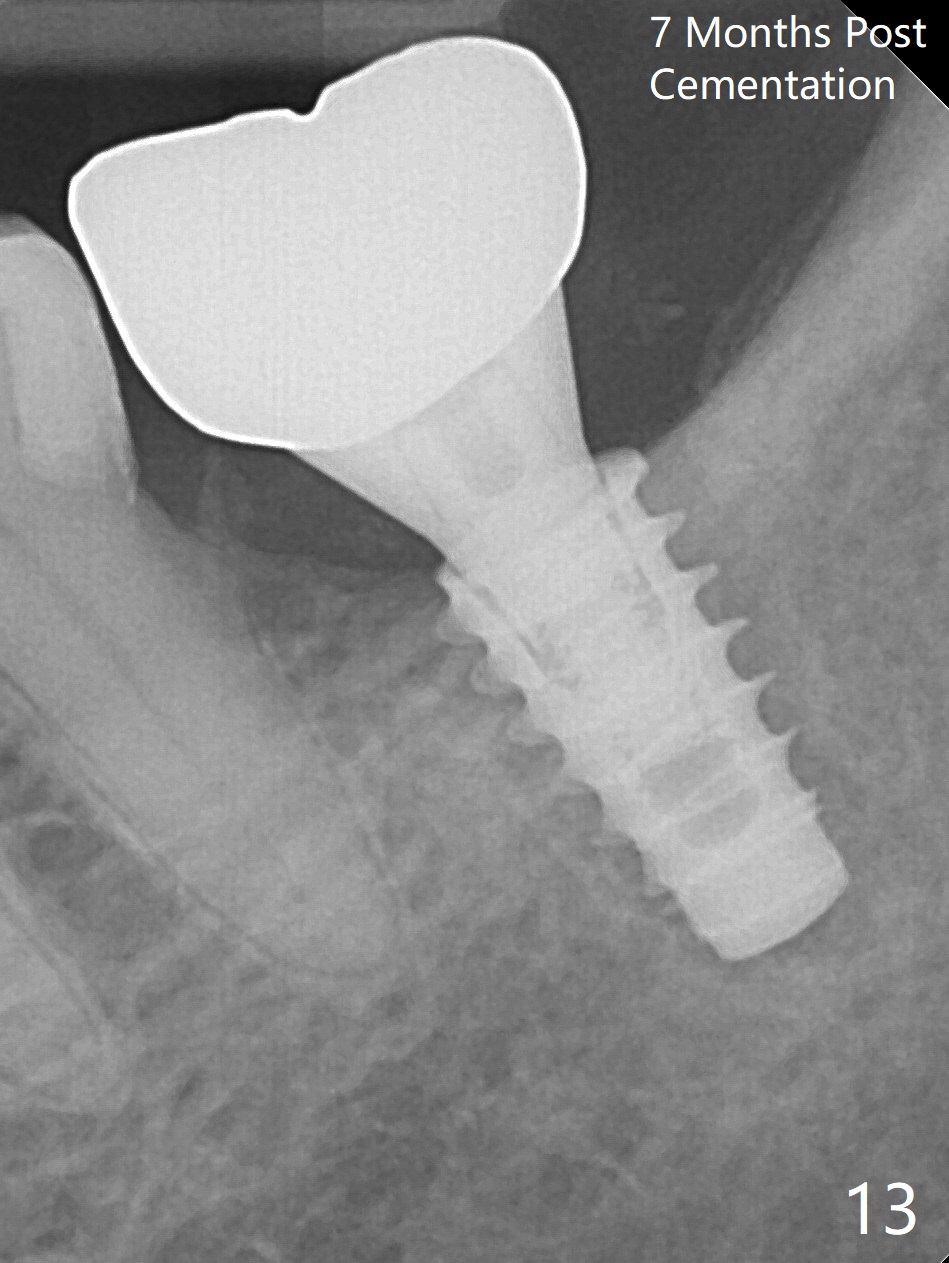

There is no apparent bone loss 4 months postop (Fig.10).  There is chewing pain in spite of occlusal adjustment 7 months post cementation (Fig.11-13: increased radiolucency around the implant).  The crown/abutment is removed and a healing abutment is placed (6x3 mm); the implant is stable.  The patient return for re-evaluation in 3 months (15 months postop); radiolucency appears to reduce (Fig.14).  But there is pain when the healing abutment is being removed.  After local anesthesia, the implant is removed with a wrench.  Following debridement of the osteototomy (intact, although tender), a 5x10 mm dummy implant with SLA surface is placed (Fig.15).  After 5.5 mm tap, a 5.5x8.5 mm implant is placed with >50 Ncm (Fig.16).  A 6.8x5 mm healing abutment is placed, followed by periodontal dressing.  Re-analysis of preop CBCT shows that the bone density at the site is low: 70 units average.  Progressive loading is necessary for this case 4-6 months postop.  The soft and hard tissues around the implant seem to heal 4 months postop (Fig.17).